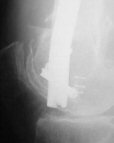

KEMMD> method of treatment for distal femur fractures

A new toy is more interesting and fashionable. And anyway it is not panacea, i have already seen presentations with LISS failures like the attached one presented by D.Seligson. And people also demonstrated incisions say that the method is not so LESS invasive as it supposed to be.